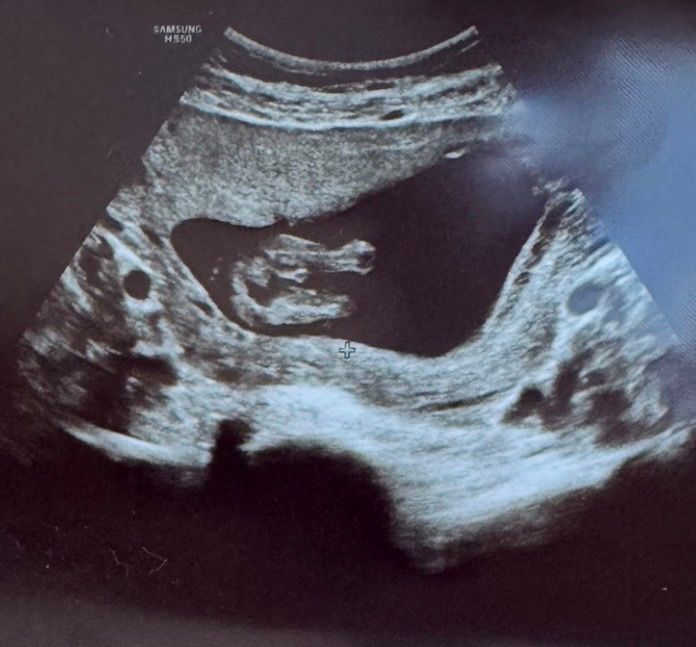

Katrinrina, сегодня была на внеплановом узи, так как утром немного кровило и была у другого узиста, сегодня мне сказали, что мальчик😂 но я все равно сомневаюсь, вот наше фото, сказала, что если была бы девочка, то так не торчало внизу, между ножками. Срок почти 15 недель у меня, у вас было такое фото? Изображение

20.12.2024

Eva , ну да, здесь уже на пацана больше смахивает) На 20 недель в этой же позе у нас было 3 складочки и ничего не выпирало) Но я почему-то до сих пор ( 26 неделя ) не могу успокоиться , не ошиблись ли, поэтому записалась на 4д скрининг в январе ) А вы как на 20 неделе сделаете - напишите , очень интересно ))